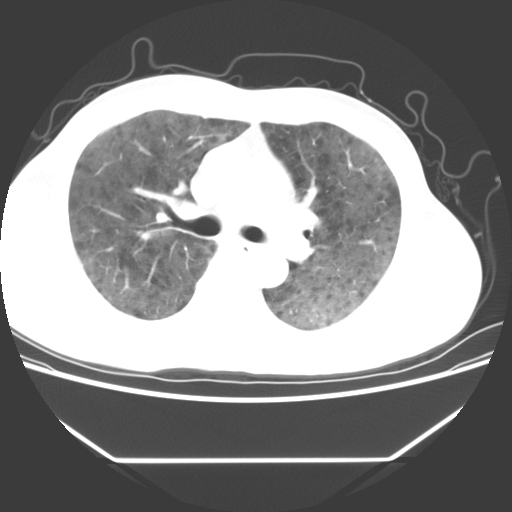

病人55岁,咳嗽,胸闷

忘了传病史了,病人55岁,咳嗽,胸闷

两肺部呈“毛玻璃”状改变,原因待查考虑感染性病变

病人是否发烧,两肺“磨玻璃”影,其间见空气支气管征和碎路石征。考虑肺泡蛋白沉着症。

两肺广泛对称磨玻璃样影,密度不均,考虑机遇性肺部感染。

双肺弥漫磨玻璃样病变,病史很重要。有感冒或发烧史,甲流不除外。无发烧可考虑肺泡蛋白沉积,但肺泡蛋白沉积边缘往往较清晰,与正常肺组织分界清晰

两肺弥漫间质性病变,考虑肺泡蛋白沉着症。建议进一步检查。

两肺“磨玻璃”影,其间见空气支气管征和碎路石征。考虑肺泡蛋白沉着症。